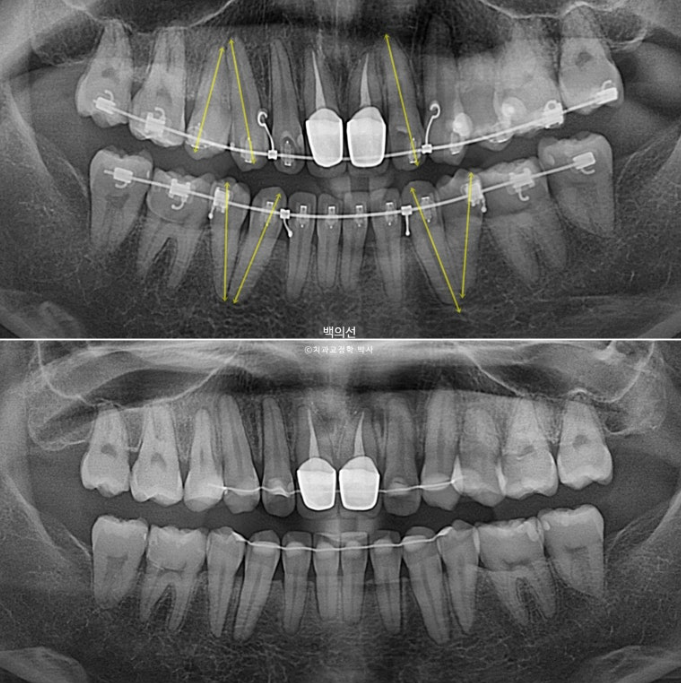

치료기간이 이미 2년 10개월이 된만큼 교정치료 마무리 단계입니다.

그런데 엑스레이상 치아 뿌리의 평행이 맞지 않는 부분들이 보입니다.

뿌리가 맞닿아 있으면 발치공간이 잘 닫히지 않을뿐더러 여러모로 좋지 않습니다.

치아 뿌리는 안 보이는 부분이지만 평행하게 맞추는 것이 장기적으로 환자분께 좋습니다.

환자분은 교정중이던 치과에 MRI촬영으로 인하여 인해 인비절라인으로 교정 방법을 바꿔 마무리 해주길 요청했었으나 기존치과에서는 인비절라인으로 뿌리이동이 안되기 때문에 발치교정은 절대 안된다. 라고

남은 공간 마무리와 치아뿌리 각도 개선, 중심선 개선을 목표로 인비절라인 라이트를 권유드렸습니다.

아까 엑스레이에서 치축이 기울어져 있던 파란화살표 측절치는 튀어나와 보이고 기울어져 보입니다.

뼈속에서 붙어있던 송곳니와 작은어금니 뿌리들은 4개월의 교정으로 비로소 서로 멀어지며 정렬을 찾았습니다.

간혹 "인비절라인 뿌리이동이 안된다더라" 라는 잘못된 정보를 물어보는 환자분들이 계십니다.